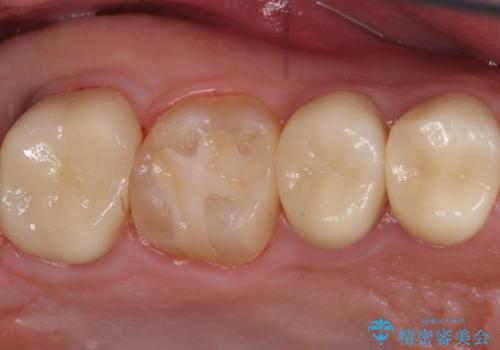

奥歯は十分な歯の高さがなかったため、クラウンをかぶせる前に歯周外科治療で歯の高さを出しています。

歯科に通うようになってから磨き残しの状態も改善されていきました。